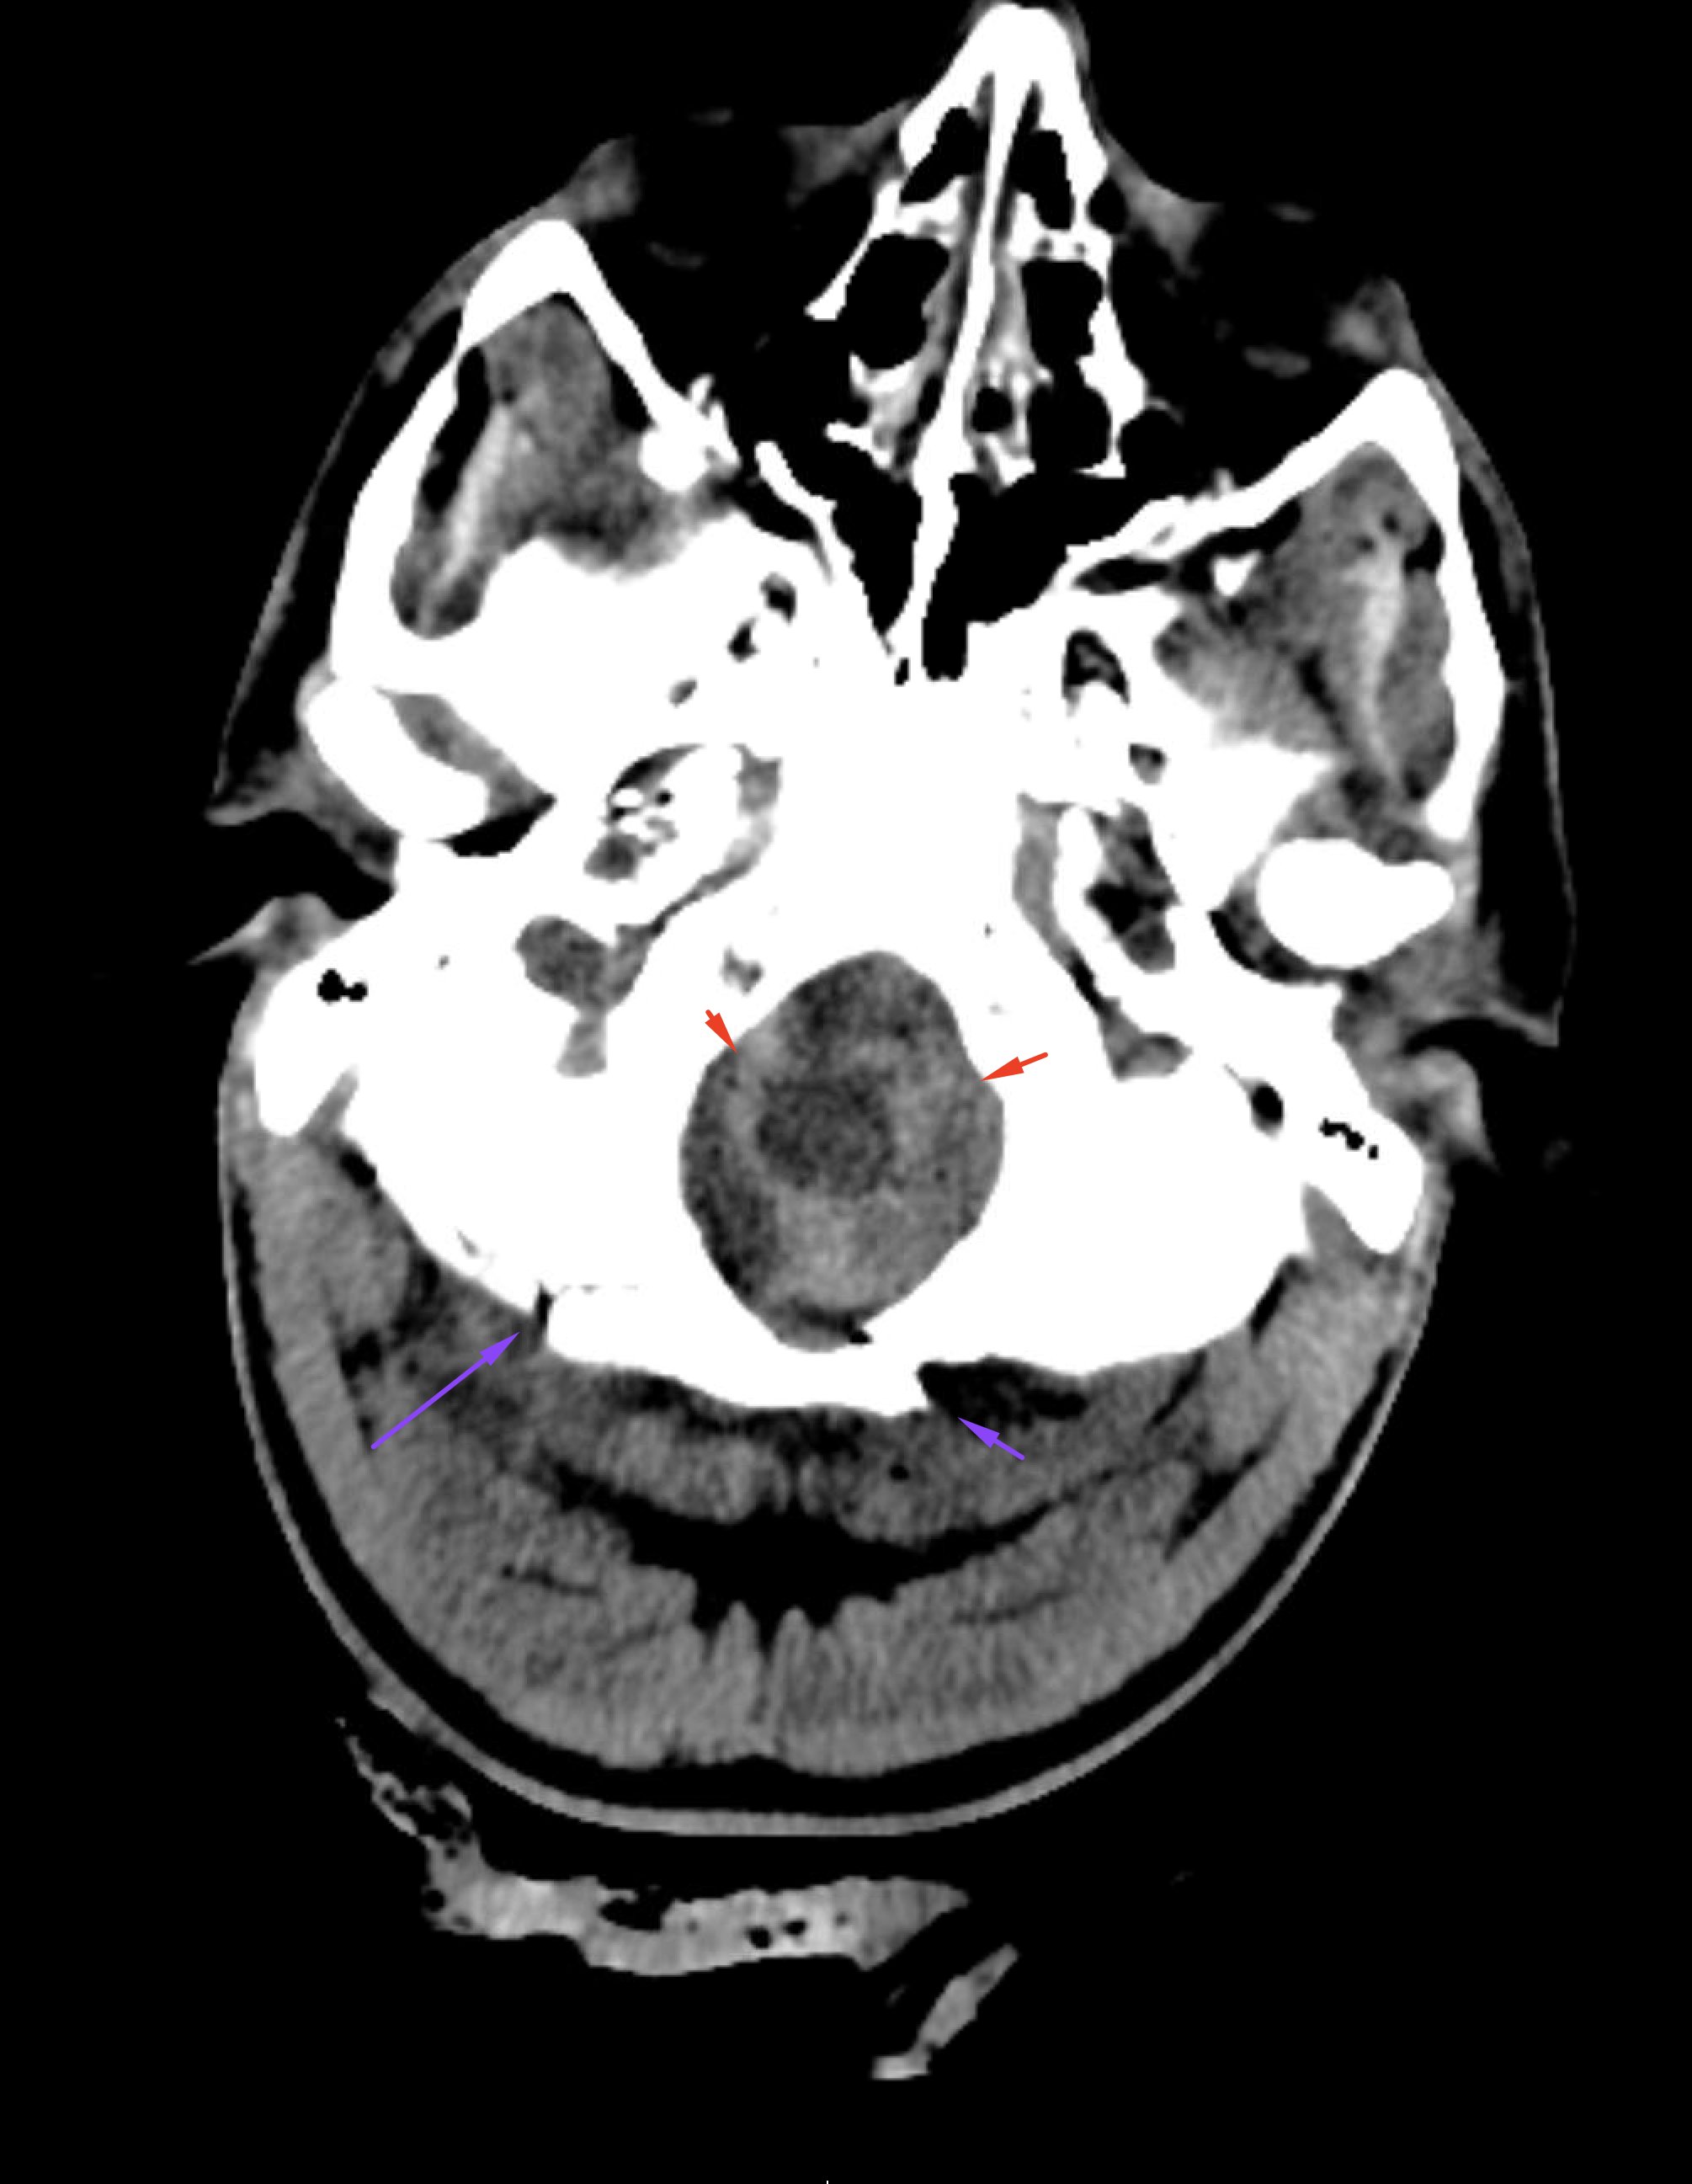

Age: Unknown

Sex: Male

Indication: Evaluate for brain death, trauma patient

Radiotracer: Tc99m ECD (ethyl cysteinate dimer)

Sample ReportNo evidence of intracranial perfusion. While not diagnostic in itself, this finding would support a clinical diagnosis of brain death.